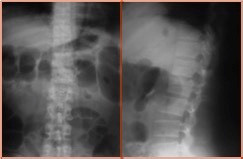

主诉:高处坠落致腰痛、活动不能1天。 现病史:患者诉于1天前不慎自3米高阳台坠落,当即感腰痛,活动不能,伴双下肢麻木。无伴昏迷、头晕等不适。遂到我院就诊,行x光检查示腰2椎体爆裂骨折,收入院。

查体:卧床状态,腰部活动不能,行走不能,腰2棘突上叩痛,压痛(+)。双下肢大腿中段以下皮肤感觉减退、肌力正常,膝反射及膝踝反射正常,双侧Babinski征(-)。 辅助检查:CT检查示腰2椎体爆裂性骨折。椎管内占位改变。

诊断:腰2椎体爆裂性骨折(AO分型:A3.1) 治疗:给予急诊行腰1-腰2椎弓根钉固定+骨折复位术。术中行椎板切除减压,用骨冲将突入椎管的骨块复位。